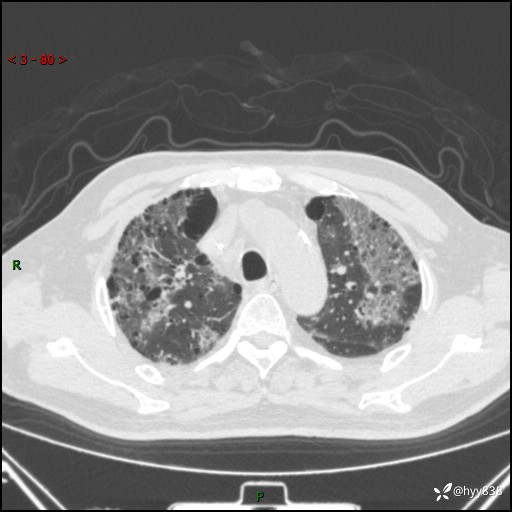

患者性别:男

患者年龄:64岁

简要病史:肝内胆管癌综合治疗后2周余,咳嗽、发热,咳白色泡沫痰。

辅助检查:CT

临床诊断:感染?

讨论:病变性质?